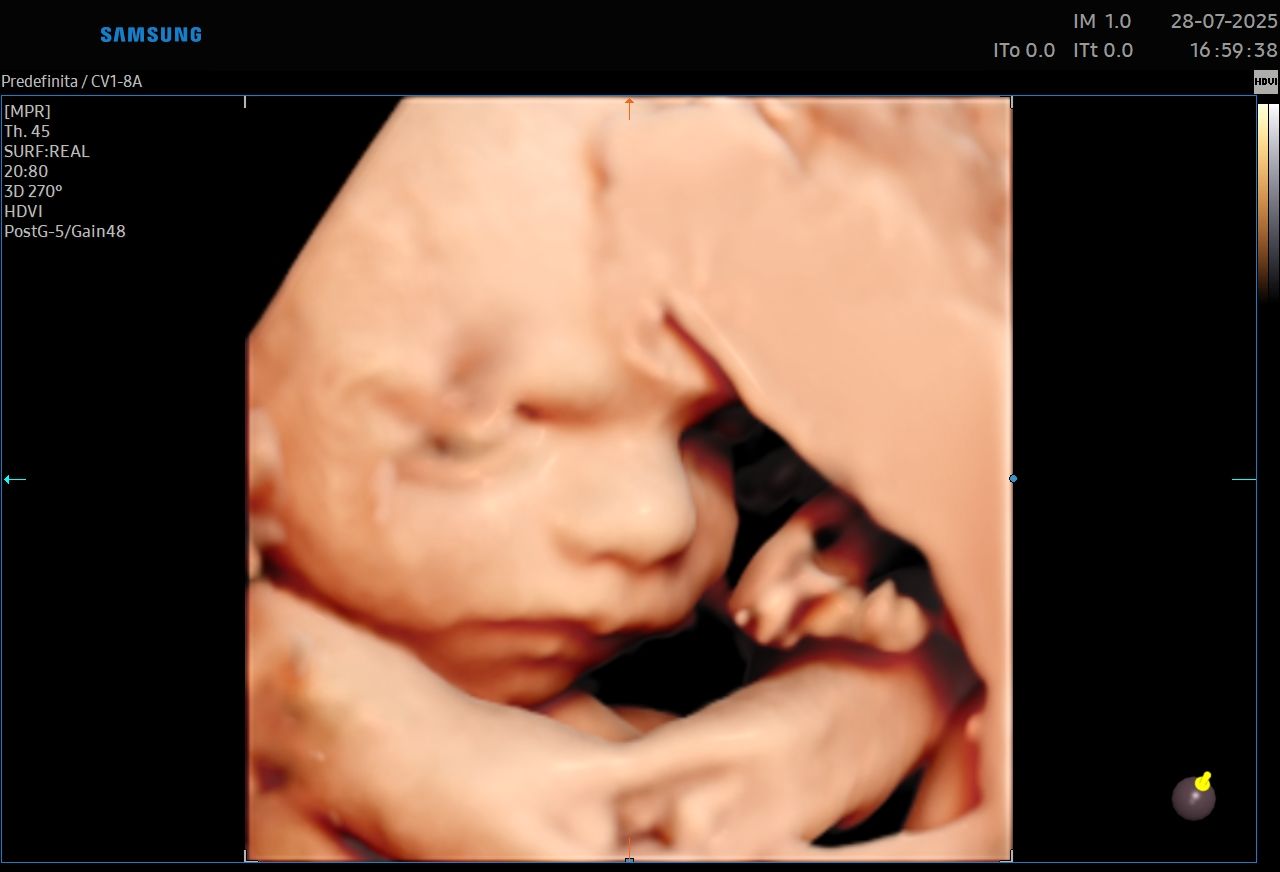

ecografia 3D ginecologica e ostetrica Da 90 €